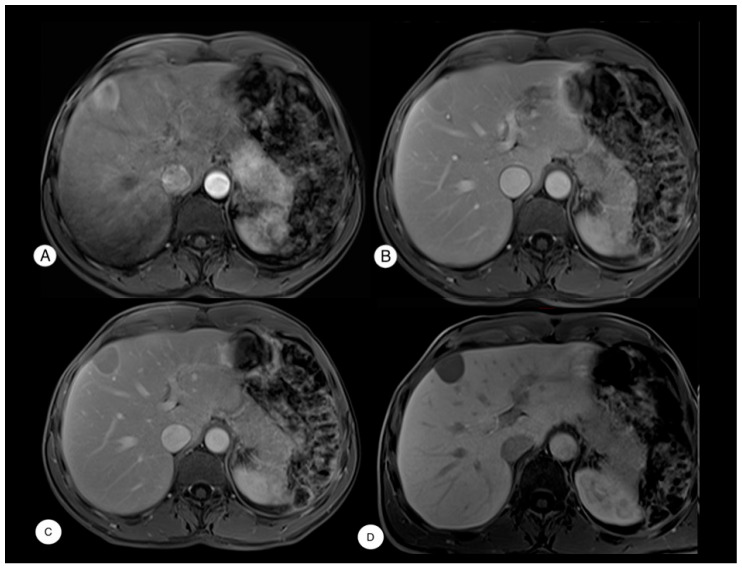

背景:肝性脾脾症(HS)是一种罕见的由脾组织异位植入引起的非生理性疾病,最常见于外伤性或外科脾切除术后。其放射学特征可能与肝细胞癌(HCC)相似,可能导致误诊和不必要的侵入性手术,如活检或肝切除术。方法:使用PubMed数据库进行文献回顾,确定所有报告的HS病例。病例介绍:我们报告一名52岁男性病例,偶然发现肝脏V段病变,最初怀疑为HCC,并有创伤后脾切除术史。患者无肝脏疾病病史。由于病变位于浅表位置,因此没有进行活检,因为存在肿瘤破裂导致出血或腹膜播种的风险。因此,患者接受了前路腹腔镜解剖切除v节段。最终病理诊断为肝内脾肿大。结论:有脾切除术史但无肝脏基础疾病的患者,特别是当影像学显示提示HCC的特征时,如动脉期高强化和门静脉冲洗时,应考虑HS作为肝脏病变的鉴别诊断。对这种实体的认识可以防止不必要的侵入性干预,并指导适当的患者管理。

Background: Hepatic splenosis (HS) is a rare para-physiological condition resulting from the ectopic implantation of splenic tissue, most commonly following traumatic or surgical splenectomy. Its radiological features can mimic those of hepatocellular carcinoma (HCC), potentially leading to misdiagnosis and unnecessary invasive procedures, such as biopsies or liver resection. Methods: A literature review was conducted using the PubMed database to identify all reported cases of HS. Case Presentation: We report the case of a 52-year-old male with an incidental finding of a liver lesion in segment V, initially suspected to be HCC, and a history of post-traumatic splenectomy. The patient had no history of underlying liver disease. Due to the lesion's superficial location, a biopsy was not performed because of the risk of tumor rupture with subsequent bleeding or peritoneal seeding. Consequently, the patient underwent upfront laparoscopic anatomic segmentectomy of segment V. Final pathology revealed a diagnosis of intrahepatic splenosis. Conclusions: HS should be considered in the differential diagnosis of liver lesions in patients with a history of splenectomy but no underlying liver disease, particularly when imaging shows features suggestive of HCC, such as arterial phase hyperenhancement and portal venous washout. Awareness of this entity may prevent unnecessary invasive interventions and guide appropriate patient management.